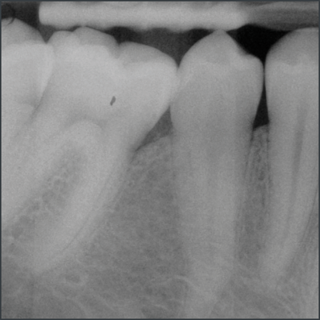

20 years after treatment with Straumann® Emdogain®.

Courtesy of Prof. Carlos Nemcovsky